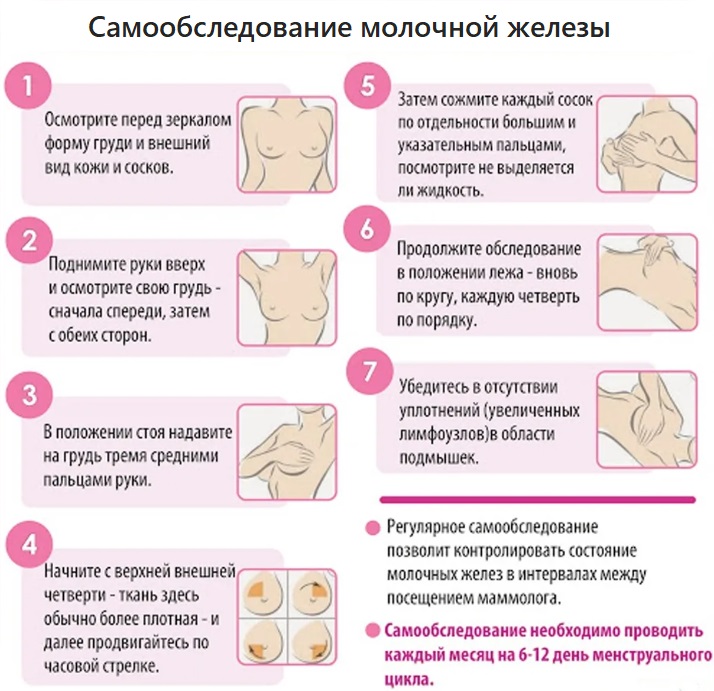

Диагностика и самообследование

Первый и регулярный шаг в сохранении здоровья груди — самопроверка. После 20 лет самостоятельное обследование стоит включить в регулярную рутину. Его задача в том, чтобы женщина хорошо узнала форму, особенности структуры своей груди и могла обратить внимание на изменения. Самопроверку стоит делать раз в месяц, желательно после завершения менструации, а в менопаузе — в одинаковые дни месяца.

Как проверить свою грудь

- найдите ростовое или поясное зеркало, которое находилось бы на уровне ваших глаз, встаньте перед ним;

- поднимите левую руку вверх, согните ее в локте и заведите ладонь за затылок;

- правой рукой осторожно ощупайте левую молочную железу по кругу, начиная сверху;

- таким же образом ощупайте правую железу левой рукой;

- легко надавите на соски, убедитесь, что из них нет выделений;

- так же по кругу ощупайте впадины подмышек.

Если вы обратили внимание на:

- любые изменения размера, формы, незначительную асимметрию груди (кроме известной вам врожденной);

- уплотнение, нагрубание ткани в молочной железе, подмышкой;

- втянутый или частично втянутый внутрь сосок;

- любые выделения из соска;

- видимые изменения кожи груди — покраснение, бугристость по типу “апельсиновой корки”, запишитесь к маммологу или гинекологу.